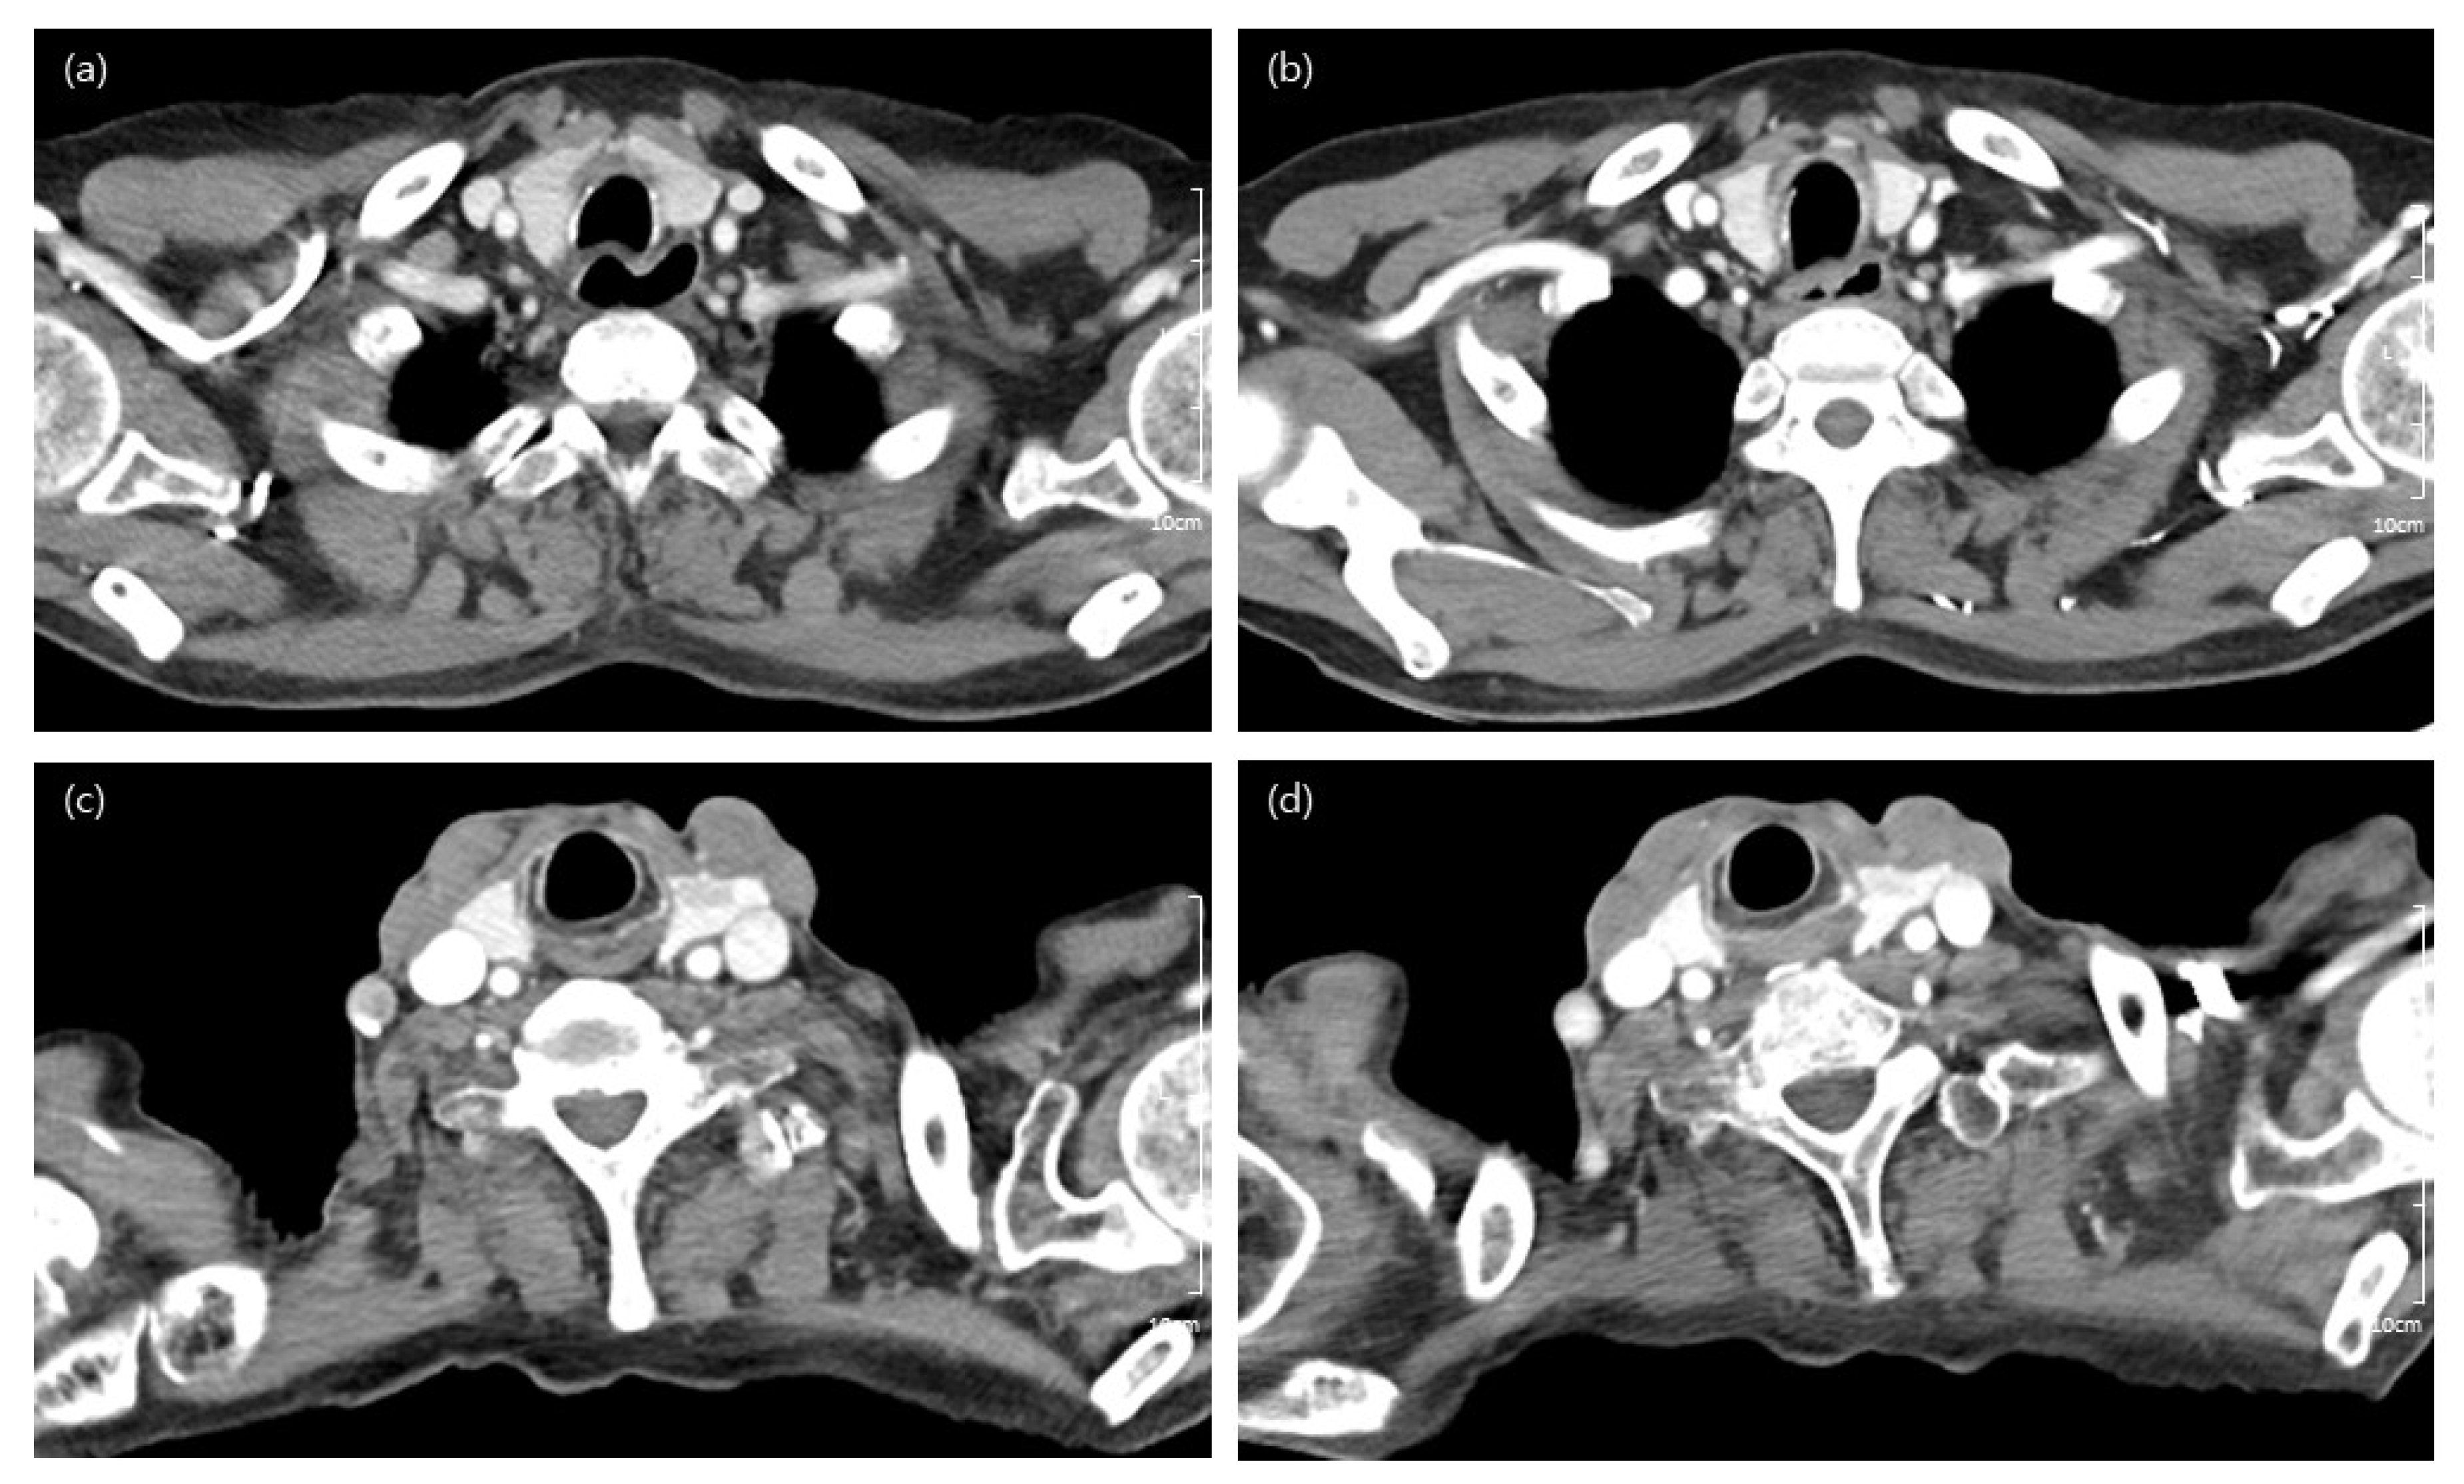

The subjective qualitative analysis results are summarized in Table 3. When comparing Group A with Group B and Group a with Group b, there were no significant differences in any of the qualitative scales; these groups showed acceptable overall image quality (Figure 3). However, images from the group that underwent CT in machine B presented significantly higher performance than those from machine A. In the subanalysis comparing machine A and machine B in terms of differences in contrast agent concentration (Tables S1 and S3) in combination with tube voltage (Tables S2 and S4), there was no difference in image quality between the two machines. The interobserver agreement of each variable was fair to good (Table 4).

Figure 3.

Computed tomography (CT) images of a 60-year-old woman obtained using low-concentration-iodine (240 mgI/mL) CM (contrast media), corresponding to Group A (a); follow-up image using high-concentration-iodine (320 mgI/mL) CM, corresponding to Group B (b). Both images have same tube voltage (100 kVp). Although there is a little streak artifact in the Group A image, both radiologists considered both images to be of good to excellent overall image quality. CT images of a 73-year-old man obtained using low-concentration-iodine (240 mgI/mL) CM and low tube voltage (90 kVp), corresponding to Group a (c); and follow-up image using high-concentration-iodine (320 mgI/mL) CM, corresponding to Group b (d). Despite the streak artifact present in the Group a image, both images were considered to exhibit good overall image quality.